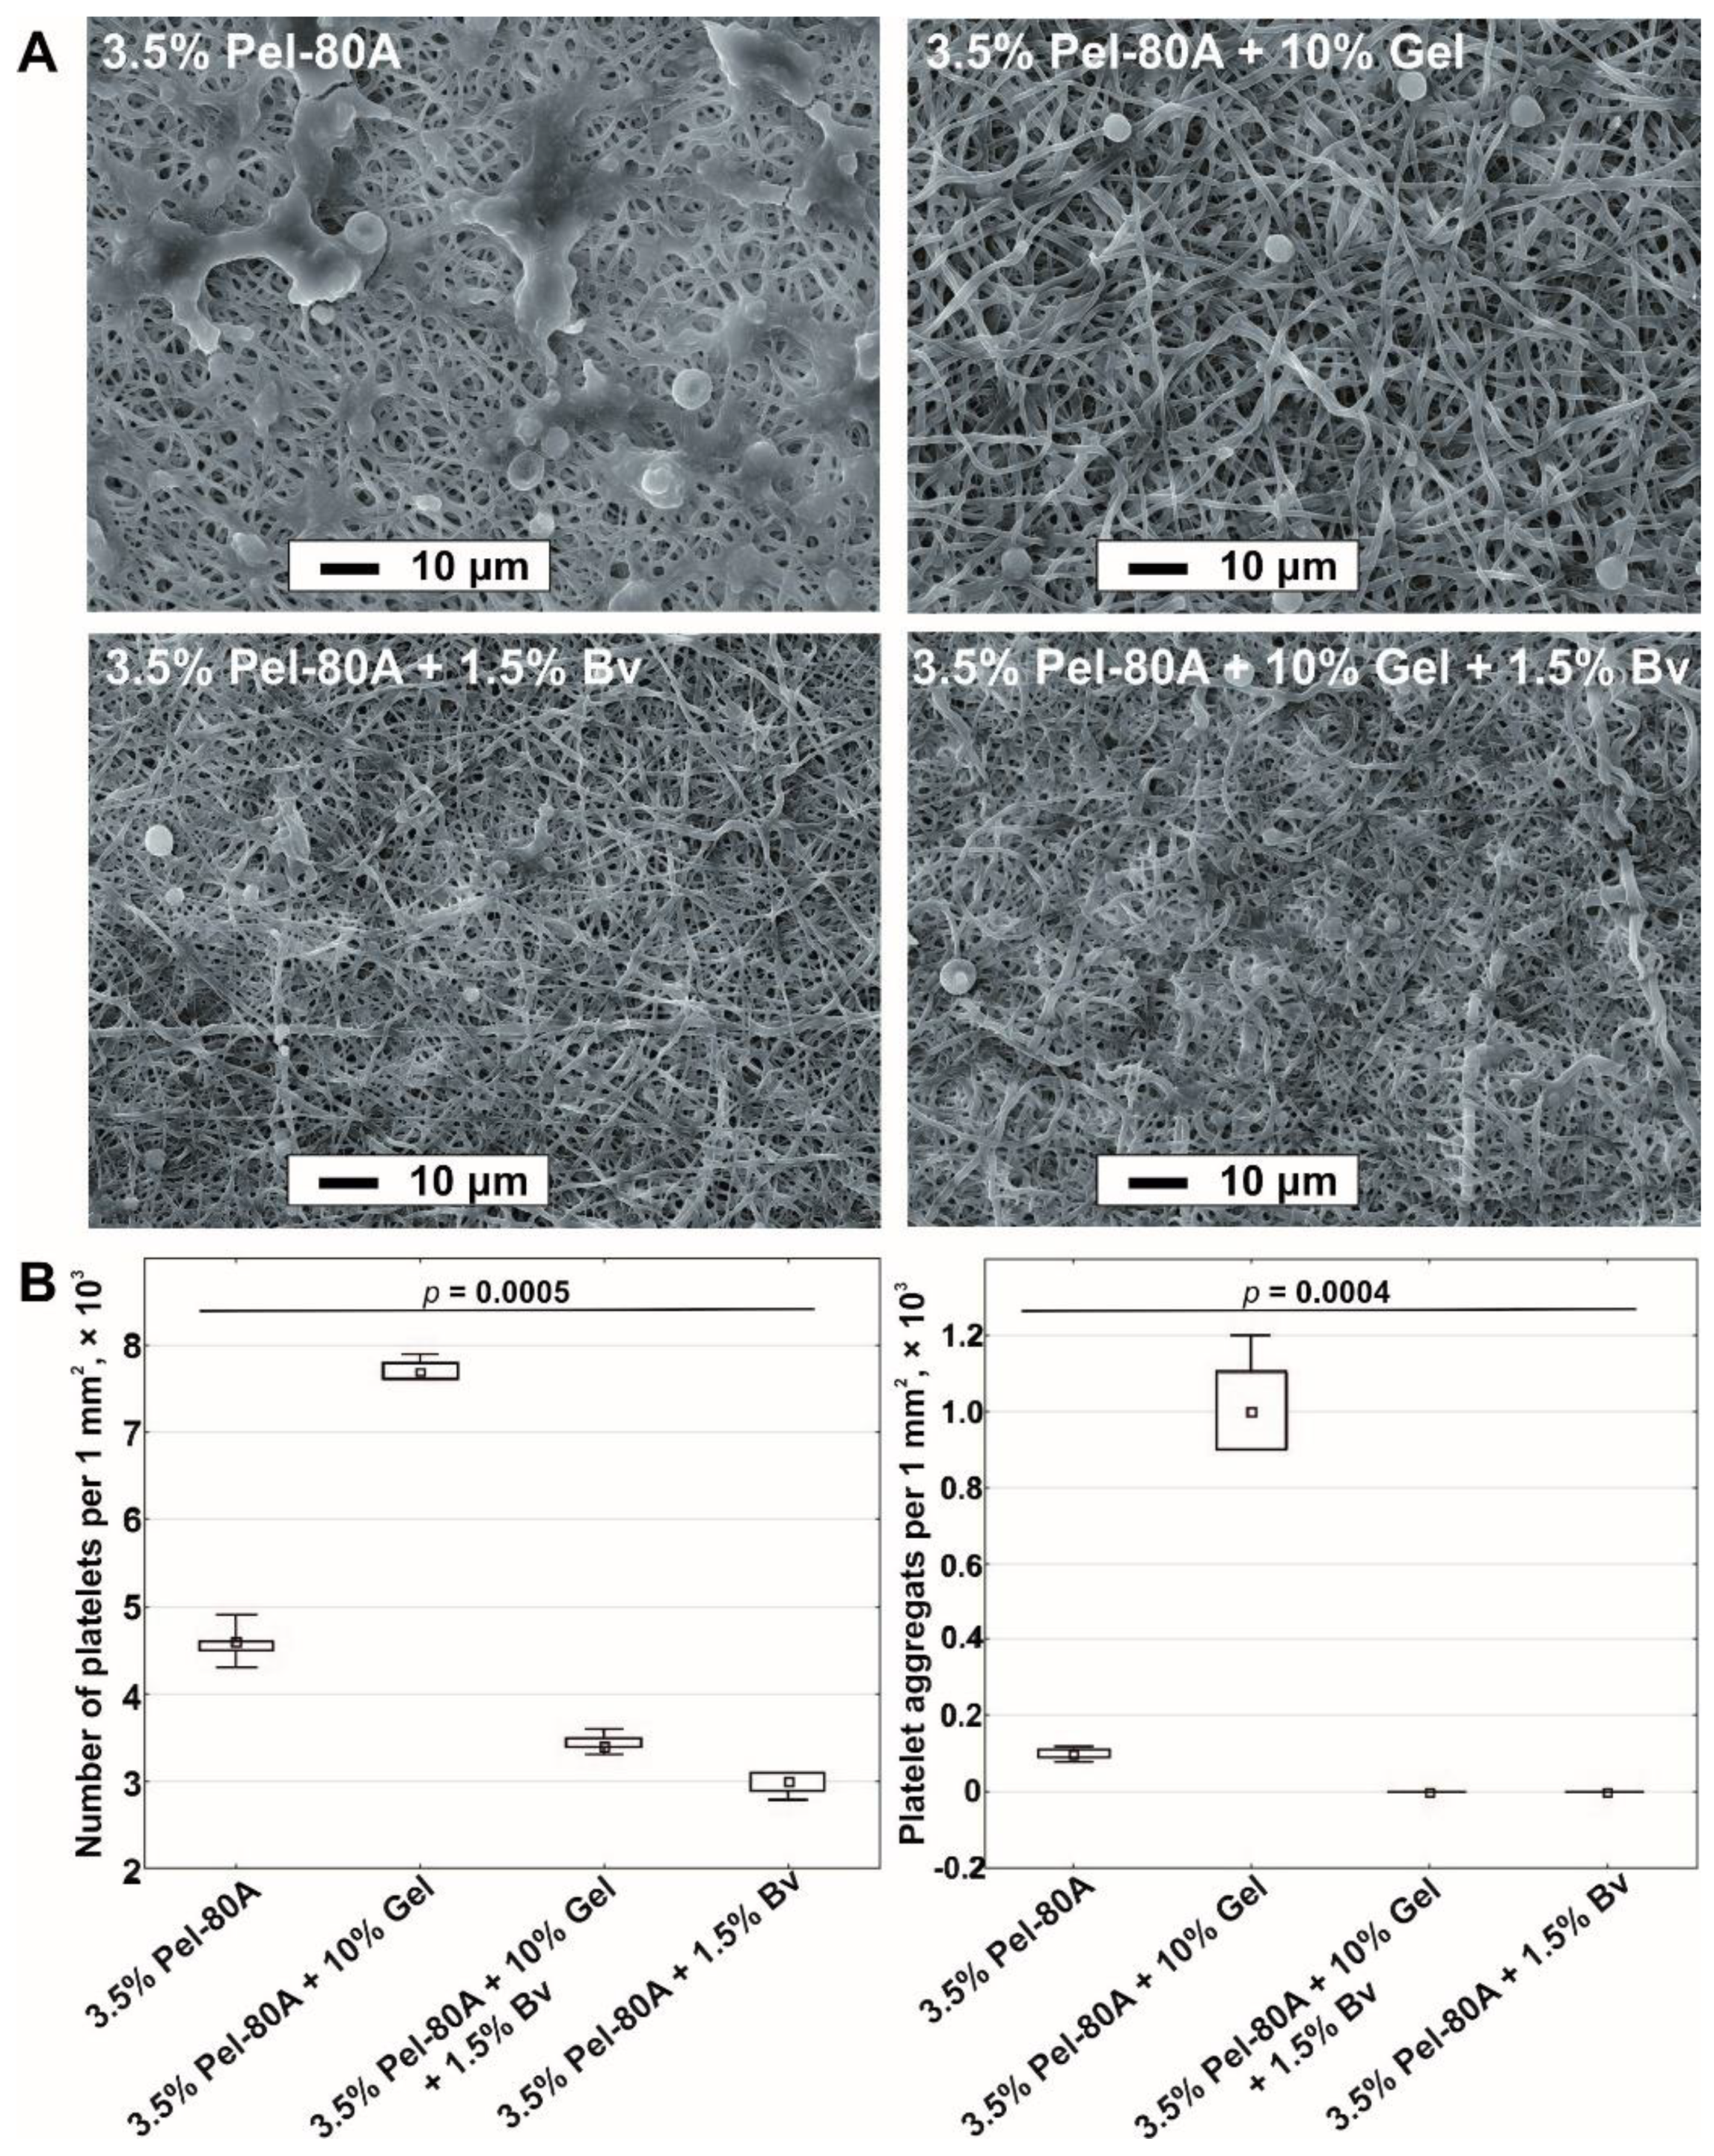

3.2. Interaction of Endothelial Cells and Blood with Matrices